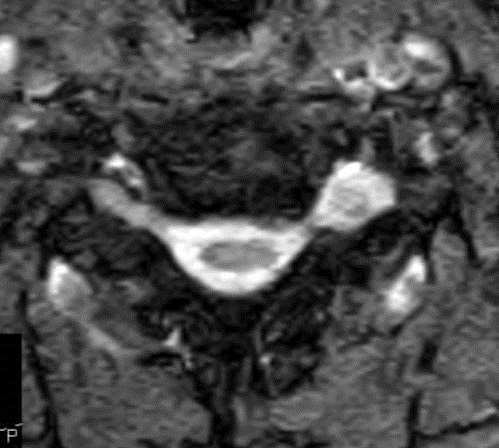

I have provided some select images from the MRI study that was obtained. Initially, the study was ordered non-contrast. Fig. 1 is a midline T-2 weighted image. It demonstrates a degree of posterior disc bulging at C6-C7. No focal posterior discal prominence was noted that would indicate a herniation. Fig. 2 is a gradient echo weighted image through the C6-C7 disc space. In this image, there is obvious expansion of the left intervertebral foramen with a degree of erosion of the facet at the posterior margin of the foramen. The signal intensity is bright on this image, compared to the normal intermediate signal intensity noted within the right foramen. You will note a degree of irregularity at the posterior margin of the disc in this cut, consistent with the disc bulging seen on the sagittal images. There is not sufficient encroachment of the central canal however to account for a neurologic deficit. A left parasagittal STIR image (Fig.3) reveals an obvious focus of abnormal signal within the left C6-C7 IVF that corresponds to the finding that was noted on the axial image. The signal intensity of this area was high on the STIR, gradient echo, and T-2 weighted images, and low on the T1 weighted images, consistent with fluid. At this point what diagnoses would you entertain, and would you order any follow-up imaging or testing?

The fluid characteristics of this lesion may be consistent with two probable considerations. It is possible that there is dilation of the dural root sleeve and that the signal represents cerebrospinal fluid. This condition is not neoplastic, but rather developmental, and does not constitute a major health concern. Another possibility is that the lesion does represent a neoplastic process. Both conditions may look similar on MRI. A rather simple way to distinguish between the two would be to perform a follow-up MRI examination with the administration of intravenous contrast (gadolinium). If the mass is neoplastic there would be expected enhancement of the mass, the signal would become brighter on the T-1 weighted postcontrast images. If the mass simply represents a fluid filled sac, such as dural root sleeve dilation or cyst, there will be no enhancement of the mass.